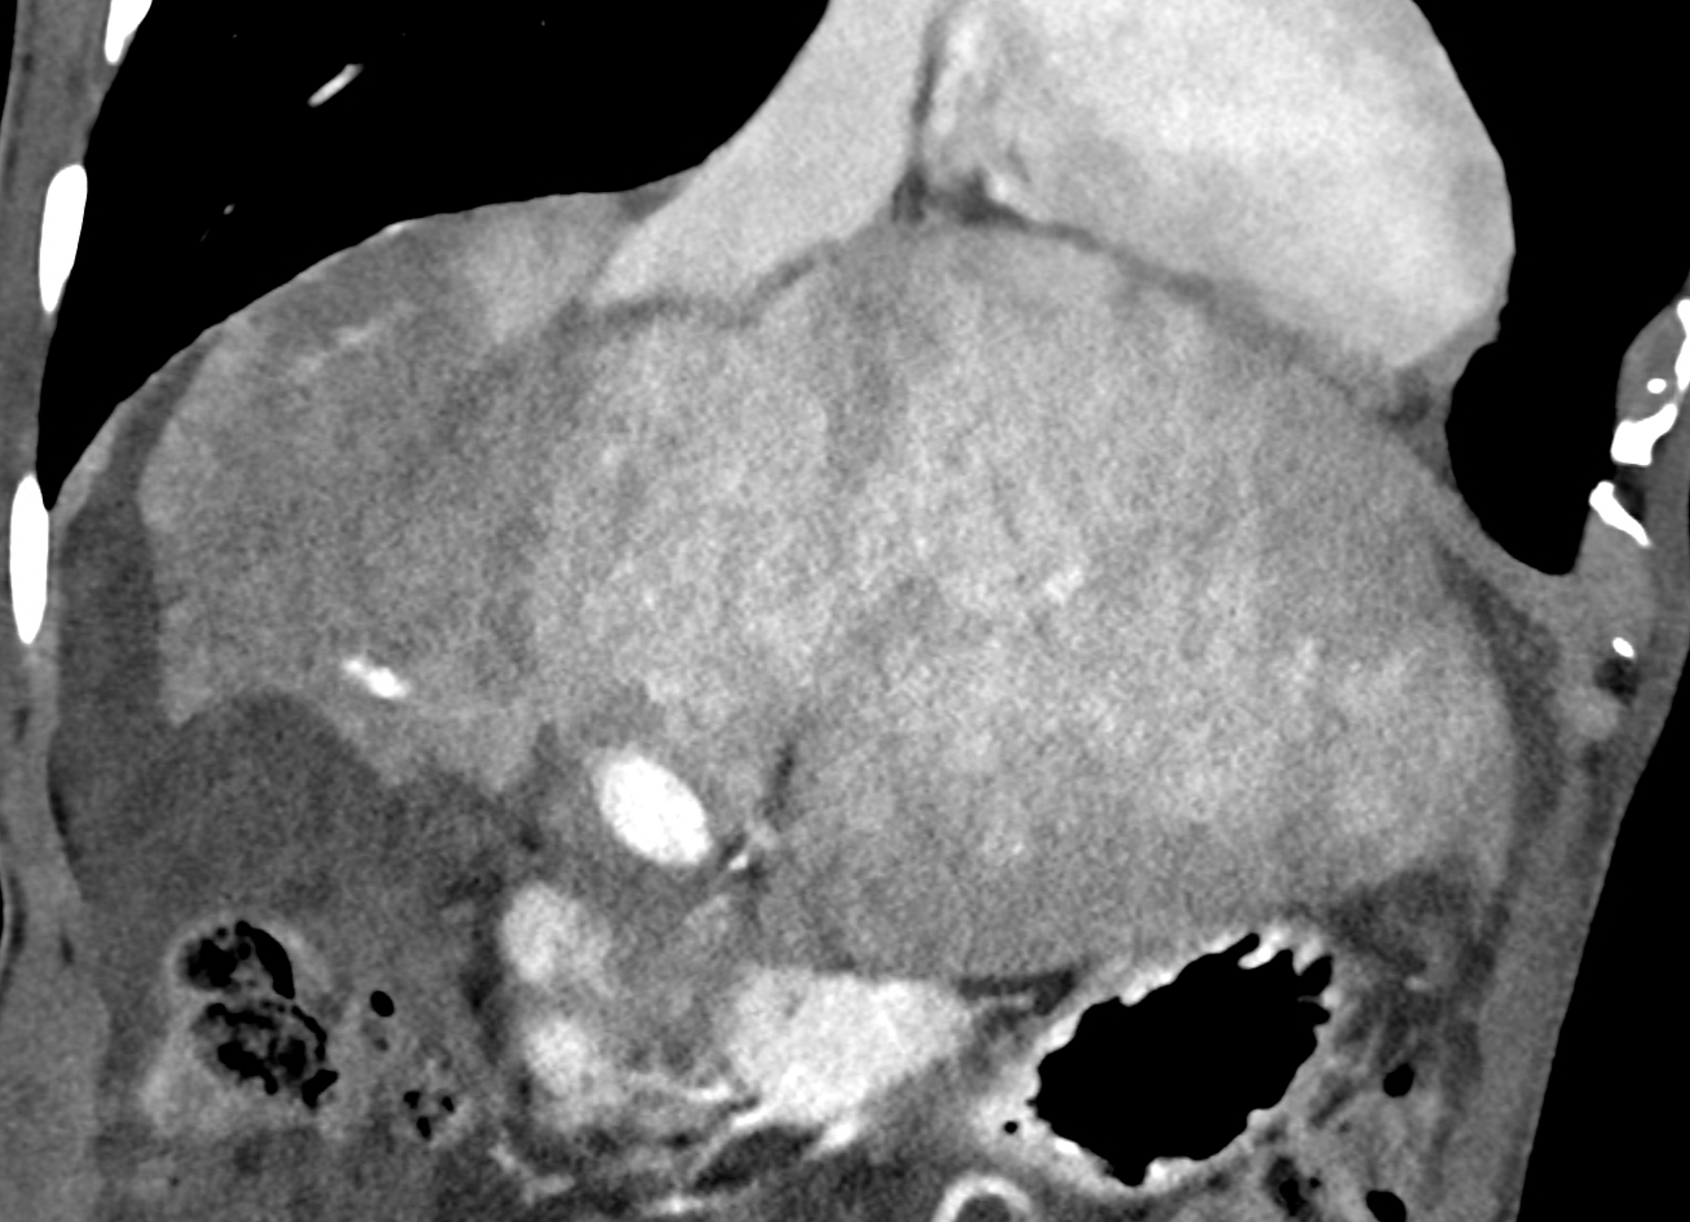

In CT images, BCS manifests as non-homogeneous enhancement of liver tissue in the arterial and especially in the portal phase, although in the portal phase may be increased, especially in the caudate lobe and left lobe, which are often hypertrophic (the hypertrophy and the enhancement is caused due to the possibility of the venous drainage directly into the inferior vena cava through the direct caudate veins), in contrast to the reduction in the right lobe. The portal vein is free, whereas even in the late phase, the hepatic veins and their contrast filling are not visible. Thrombotic occluded veins are hypodense.

A patient in his sixties with a Leiden mutation of factor V and a heterozygous prothrombin mutation presents with abdominal pain. Ultrasound examination reveals ascites and enlargement of the liver.There is enlargement of the liver, particularly the left lobe and caudate lobe. The hepatic veins are centrally filled with contrast medium due to reflux at the confluence with the inferior vena cava, and their radicular parts are thrombosed. There is typical chronic liver remodelling and the formation of centrifugal collateral circulation, including esophageal varices, and ascites is present in the abdominal cavity.

the axial images in the arterial, and the portal phases

coronary view documenting splenomegaly, different enhancement of the liver parenchyma, and ascites, the arterial, and the portal phases